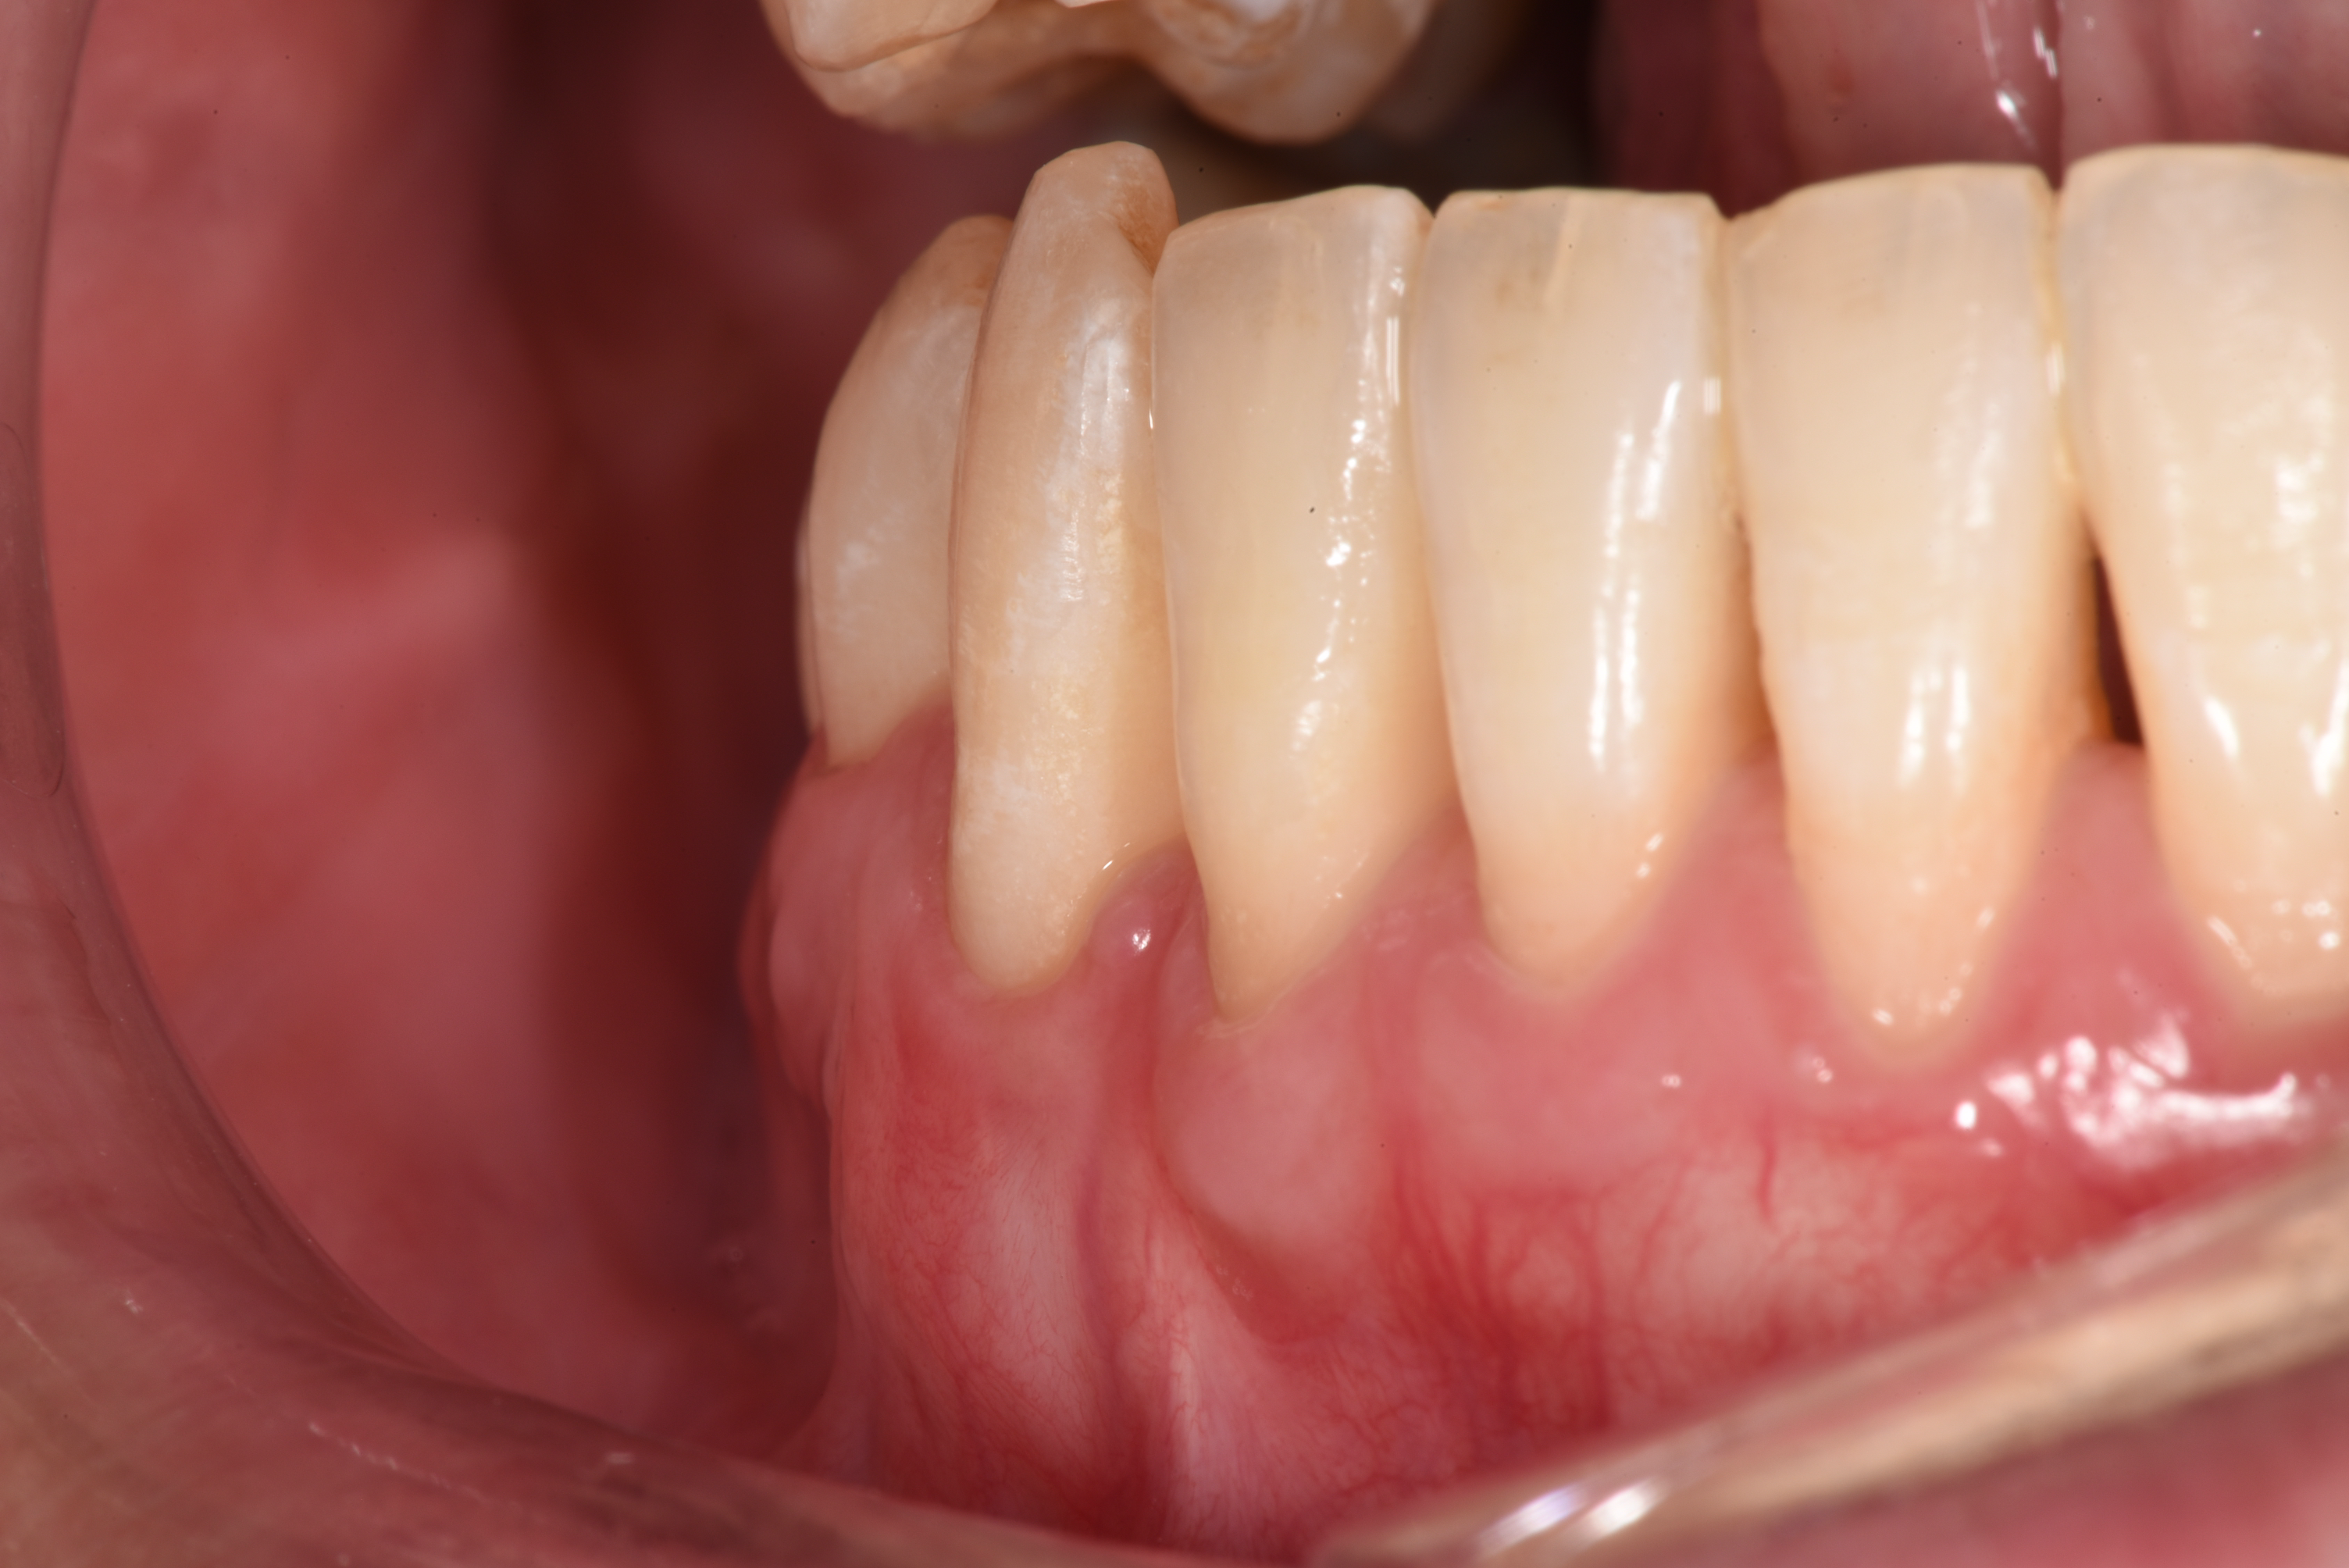

After gum surgery: the previously exposed root of the lower right canine is now almost completely covered